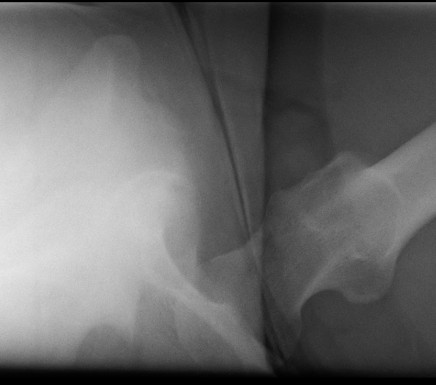

Posterior dislocation

- leg shortened, flexed, adducted & internally rotated

- head small on xray

Anterior dislocation

- leg short and externally rotated

- head larger on xray